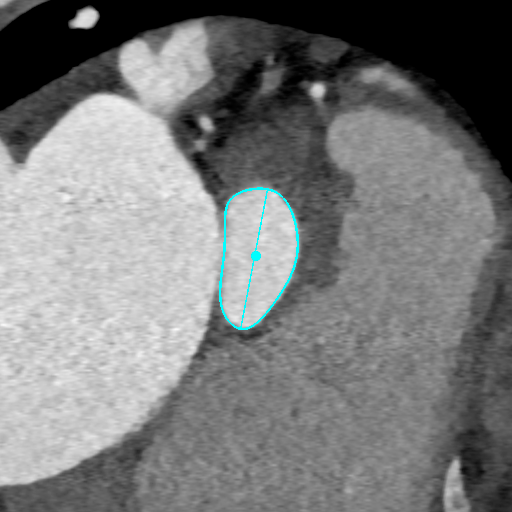

CT测量

主动脉根部CT

瓣环平均直径:

22mm

左室流出道平均直径:

23.3mm

窦宽:32/30/31mm

横位心:48°

左冠开口高度:

13.5mm

右冠开口高度:

10mm